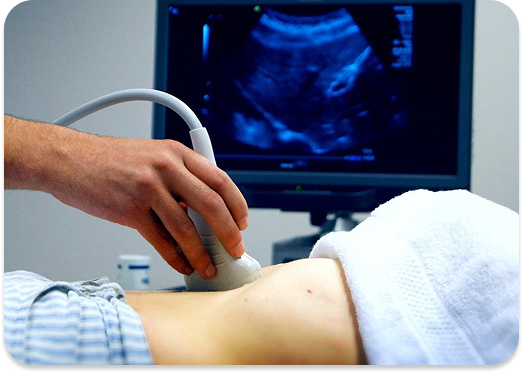

Ultrasound at Karan Hospital is a safe, radiation-free diagnostic tool that provides real-time imaging of internal organs and soft tissues. From pregnancy monitoring to detecting abdominal, pelvic, and vascular conditions—our expert radiologists and high-resolution machines ensure precision and comfort.

Ultrasound, or sonography, is a non-invasive diagnostic imaging technique that uses high-frequency sound waves to create live images of the inside of your body. It’s commonly used to examine the abdomen, liver, kidneys, uterus, ovaries, thyroid, heart, and during pregnancy. Unlike X-rays, it does not use ionising radiation, making it extremely safe—even for pregnant women. Timely ultrasounds can guide proper treatment, reduce complications, and improve patient outcomes.

Ultrasound is a safe imaging test that uses sound waves to view organs, tissues, or unborn babies.